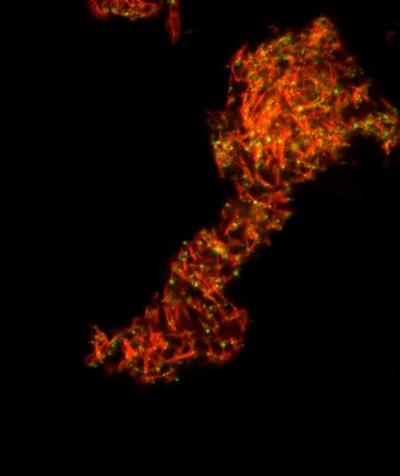

Amyloid fibrils in semen, shown here in red, enhance HIV infection by helping HIV -- shown in green -- find and attach to its target, CD4 T white blood cells.

(Photo Credit: Nadia Roan/Gladstone Institutes)